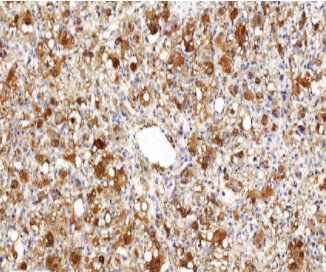

Protein Gene Product 9.5(PGP 9.5)抗体是一种高度敏感且广泛应用的神经内分泌标志物,特异性识别神经元特异性泛素羧基末端水解酶(UCH-L1)。该抗体能有效标记神经元胞体、轴突及各种神经内分泌细胞,在病理诊断中主要用于神经内分泌肿瘤(如类癌、副神经节瘤)、神经母细胞瘤和黑色素瘤的鉴别。其独特优势在于能清晰显示皮肤神经纤维网结构,对评估神经浸润和微小神经纤维瘤具有重要价值,同时在阿尔茨海默病等神经退行性病变研究中可作为神经元完整性评估的可靠指标。